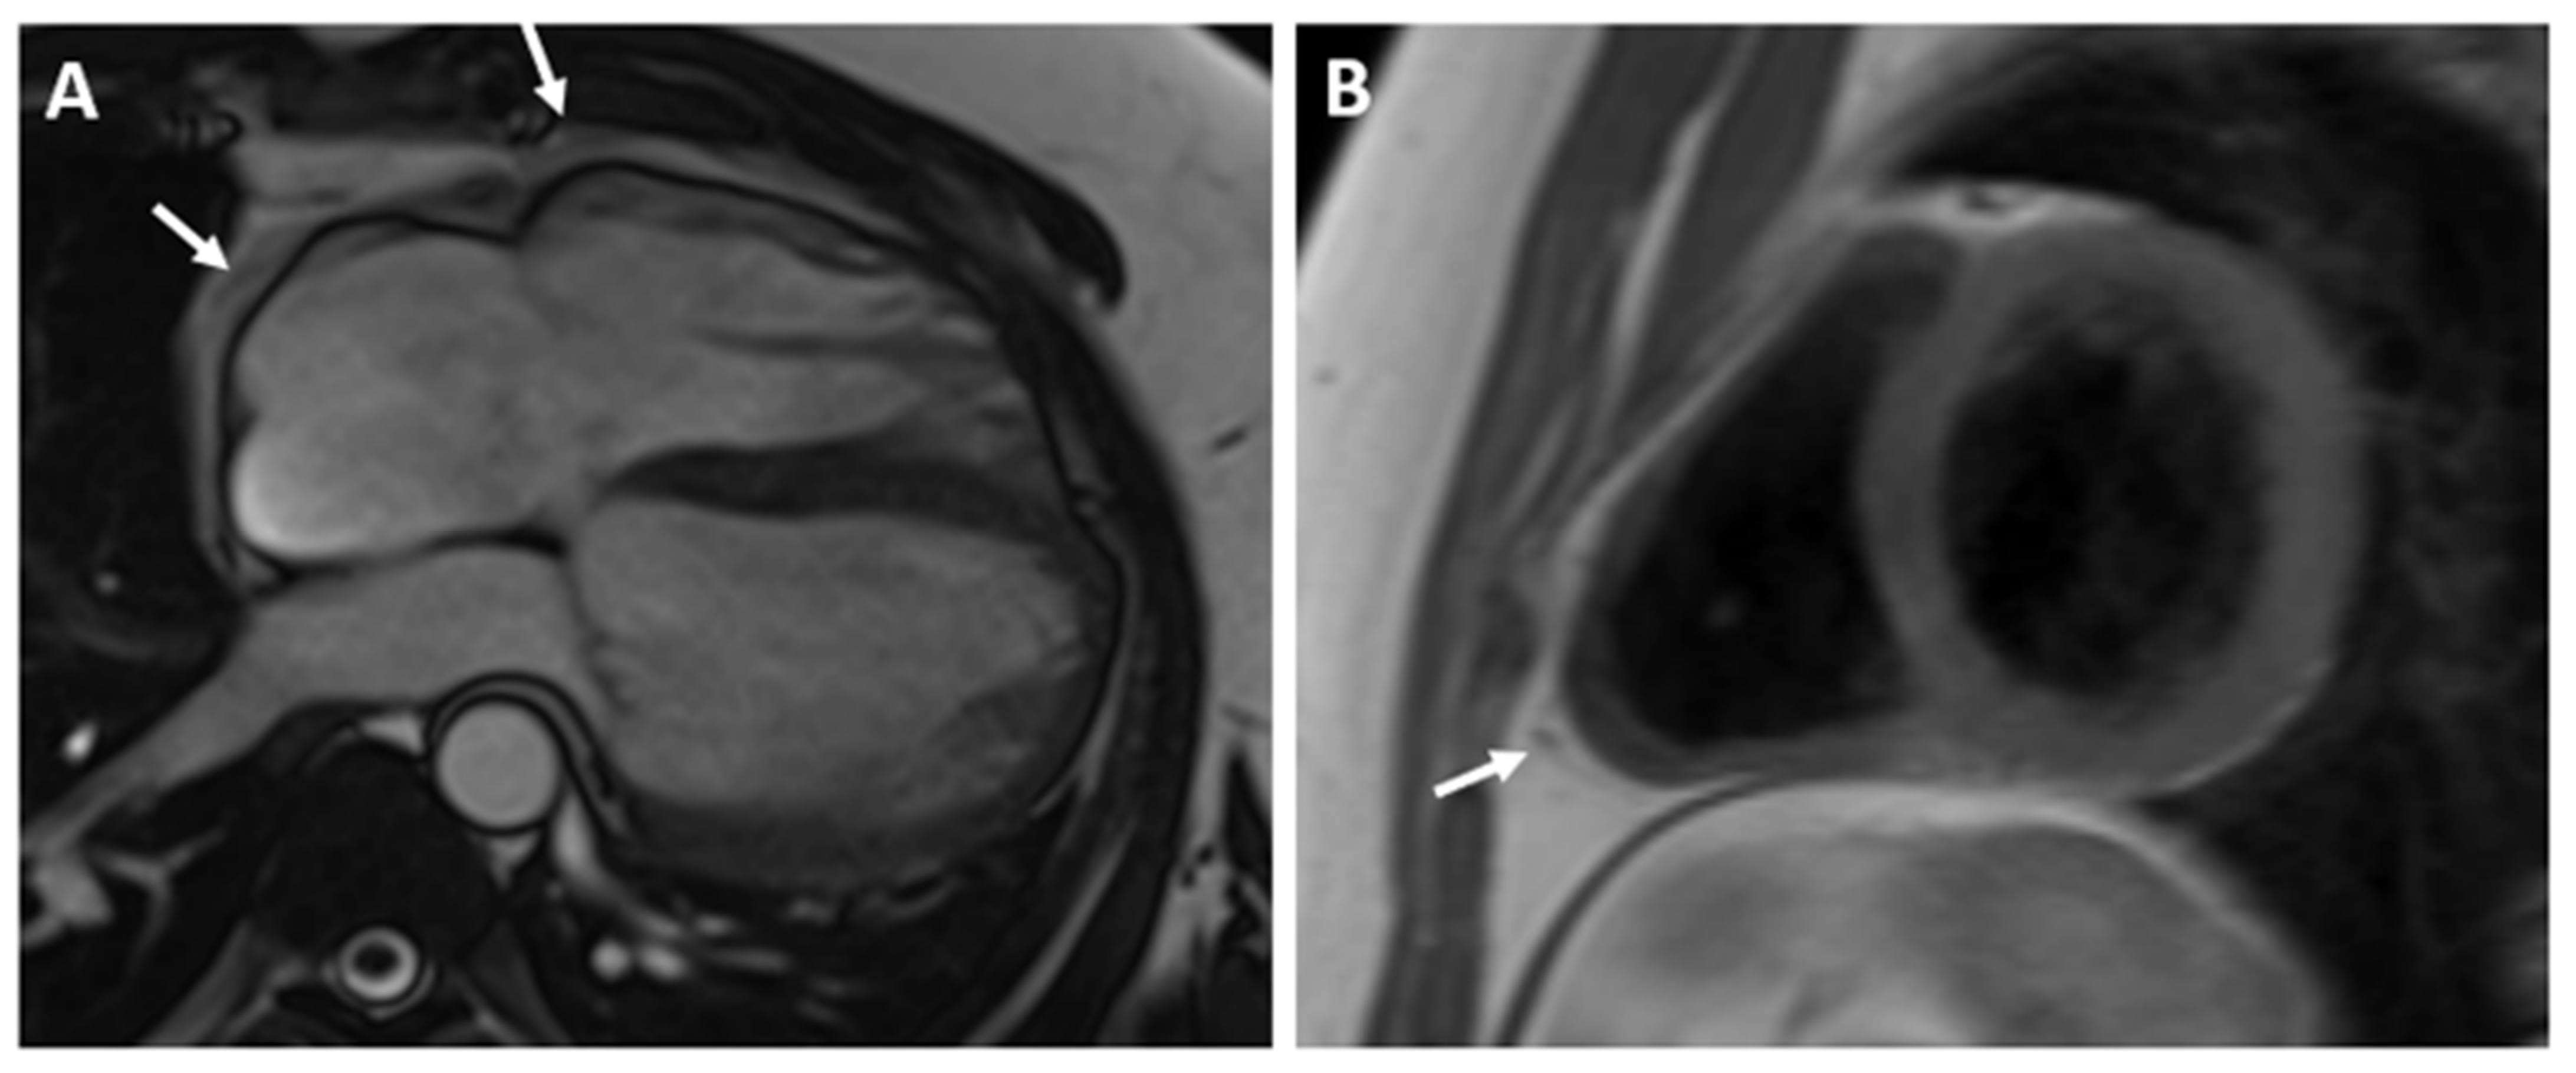

The CMR confirmed the abnormal position of the heart in the left hemithorax with laterally and posteriorly displaced apex and interposition of the lung tissue between the aorta and pulmonary trunk. There was no detectable pericardium overlying the left ventricular wall, and only a small discontinuous segments of pericardium were visualized surrounding the right atrium and right ventricular lateral wall (Figure 3 and Figure 4). Biventricular volumes and function were in the reference range. Additionally, a patent foramen ovale was visualized with no significant left-to-right shunt (Qp/Qs = 1.1).

Figure 3. (A)—Axial image of the chest shows the displacement of the heart into the left hemithorax with the cardiac apex pointing laterally and posteriorly. (B)—Coronal image of the chest demonstrates the interposition of lung tissue between the aorta and pulmonary artery (white arrow). Ao—aorta; PA—pulmonary artery.